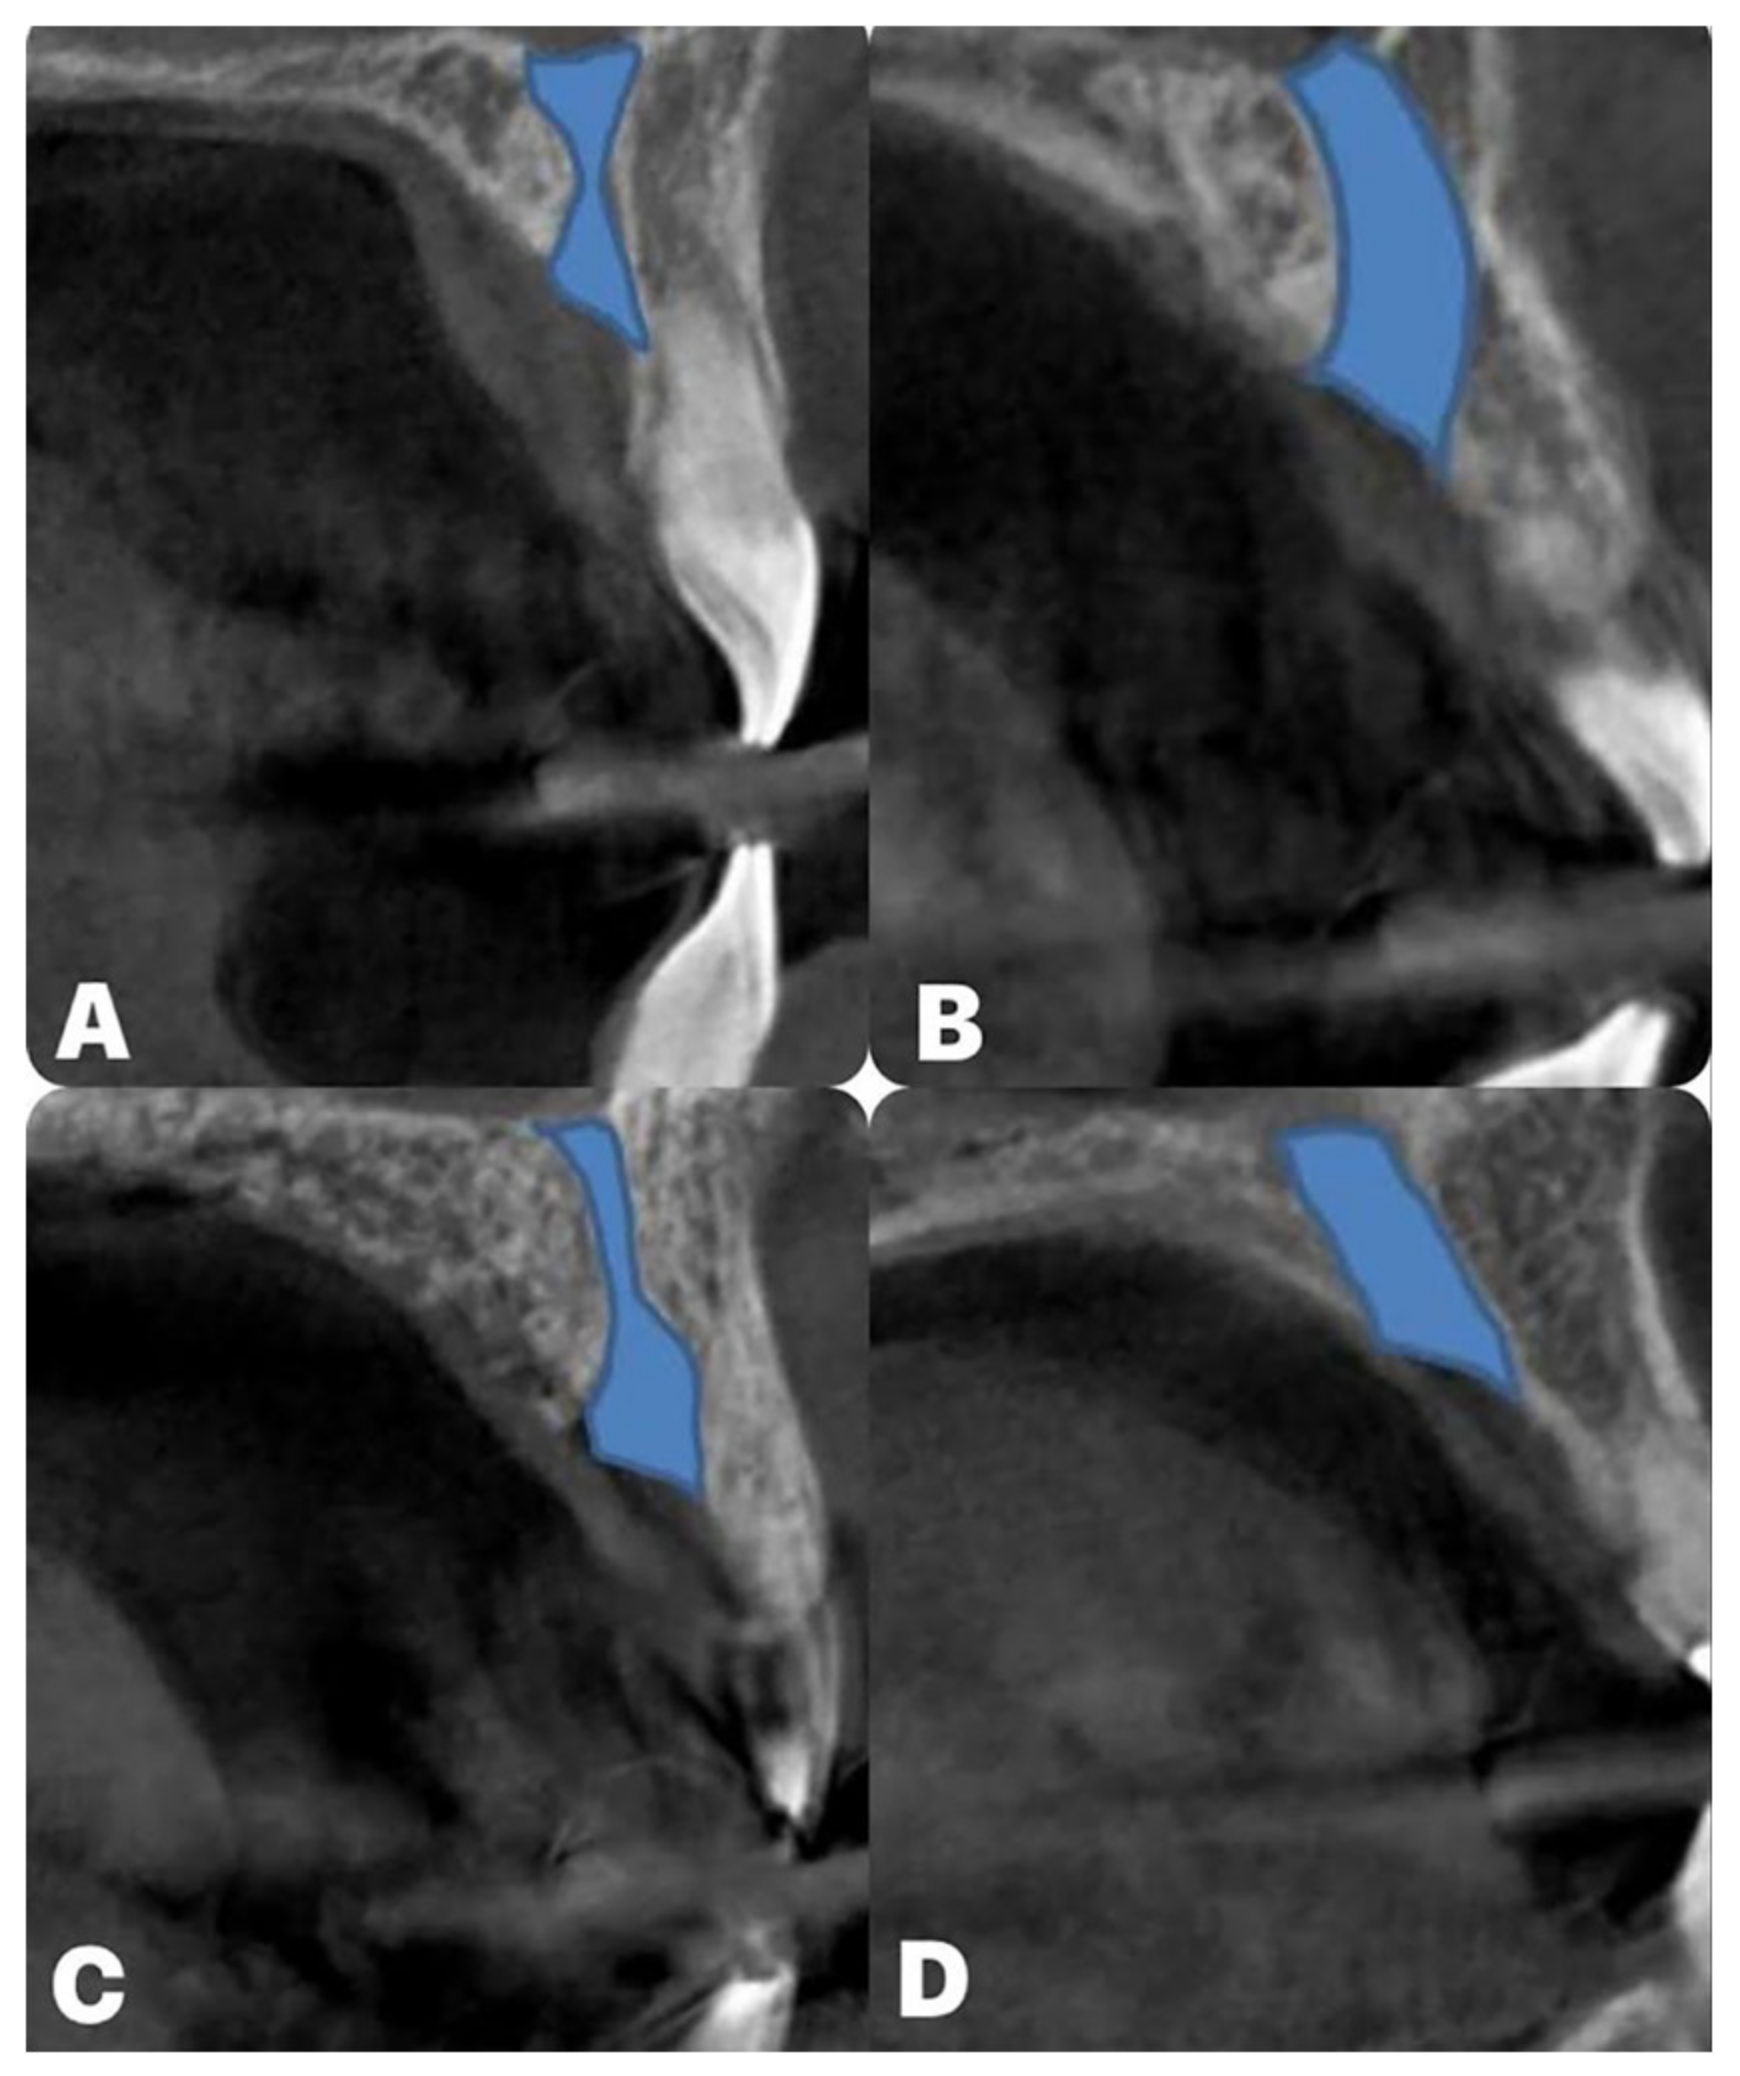

- Arnaut, A.; Milanovic, P.; Vasiljevic, M.; Jovicic, N.; Vojinovic, R.; Selakovic, D.; Rosic, G. The Shape of Nasopalatine Canal as a Determining Factor in Therapeutic Approach for Orthodontic Teeth Movement—A CBCT Study. Diagnostics 2021, 11, 2345. [Google Scholar] [CrossRef] [PubMed]

- Milanovic, P.; Selakovic, D.; Vasiljevic, M.; Jovicic, N.U.; Milovanović, D.; Vasovic, M.; Rosic, G. Morphological Characteristics of the Nasopalatine Canal and the Relationship with the Anterior Maxillary Bone—A Cone Beam Computed Tomography Study. Diagnostics 2021, 11, 915. [Google Scholar] [CrossRef] [PubMed]

- Gil-Marques, B.; Sanchis-Gimeno, J.A.; Brizuela-Velasco, A.; Perez-Bermejo, M.; Larrazábal-Morón, C. Differences in the shape and direction-course of the nasopalatine canal among dentate, partially edentulous and completely edentulous subjects. Anat. Sci. Int. 2020, 95, 76–84. [Google Scholar] [CrossRef] [PubMed]

- Safi, Y.; Moshfeghi, M.; Rahimian, S.; Kheirkhahi, M.; Manouchehri, M.E. Assessment of Nasopalatine Canal Anatomic Variations Using Cone Beam Computed Tomography in a Group of Iranian Population. Iran. J. Radiol. 2017, 14, e13480. [Google Scholar] [CrossRef]

- Bahşi, I.; Orhan, M.; Kervancıoğlu, P.; Yalçın, E.D.; Aktan, A.M. Anatomical evaluation of nasopalatine canal on cone beam computed tomography images. Folia. Morphol. 2019, 78, 153–162. [Google Scholar] [CrossRef] [PubMed]

- Güncü, G.N.; Yıldırım, Y.D.; Yılmaz, H.G.; Galindo-Moreno, P.; Velasco-Torres, M.; Al-Hezaimi, K.; Al-Shawaf, R.; Karabulut, E.; Wang, H.L.; Tözüm, T.F. Is there a gender difference in anatomic features of incisive canal and maxillary environmental bone? Clin. Oral Implants Res. 2013, 24, 1023–1026. [Google Scholar] [CrossRef] [PubMed]